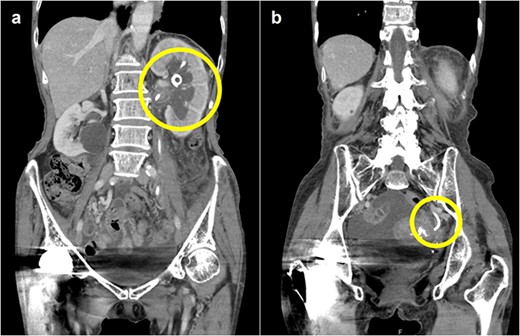

Forty-five days after the stent placement, the patient visited the emergency department complaining of fever and hematuria. CT showed that the left hydronephrosis had reappeared, and the lower end of the stent had migrated into the ureter (Fig. 3a and b). Blood tests revealed a worsening of renal function and a prominently elevated inflammatory response. Due to the diagnosis of relapse of left obstructive acute pyelonephritis caused by the migration of the ureteral stent, an emergency nephrostomy was performed promptly, and antibiotic treatment was started. The patient was discharged after 2 weeks of hospitalization.

Abdominal CT scan; (a) CT demonstrates the position of proximal coil formation in the left renal pelvis; (b) CT demonstrates proximal stent migration into the ureter.